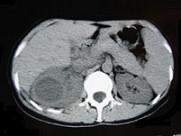

问题 女,33岁,右胁腹痛7天,尿检可见大量的脓细胞,CT平扫+增强如图所示,下列说法正确的是 ( )

选项 A.右肾体积增大,其内可见类圆形低密度病灶 B.增强扫描可见该病灶不均匀强化,其内有无强化的坏死灶 C.右肾病灶边界模糊不清 D.考虑为右肾囊肿合并感染 E.考虑为右肾脓肿

答案 ABCE